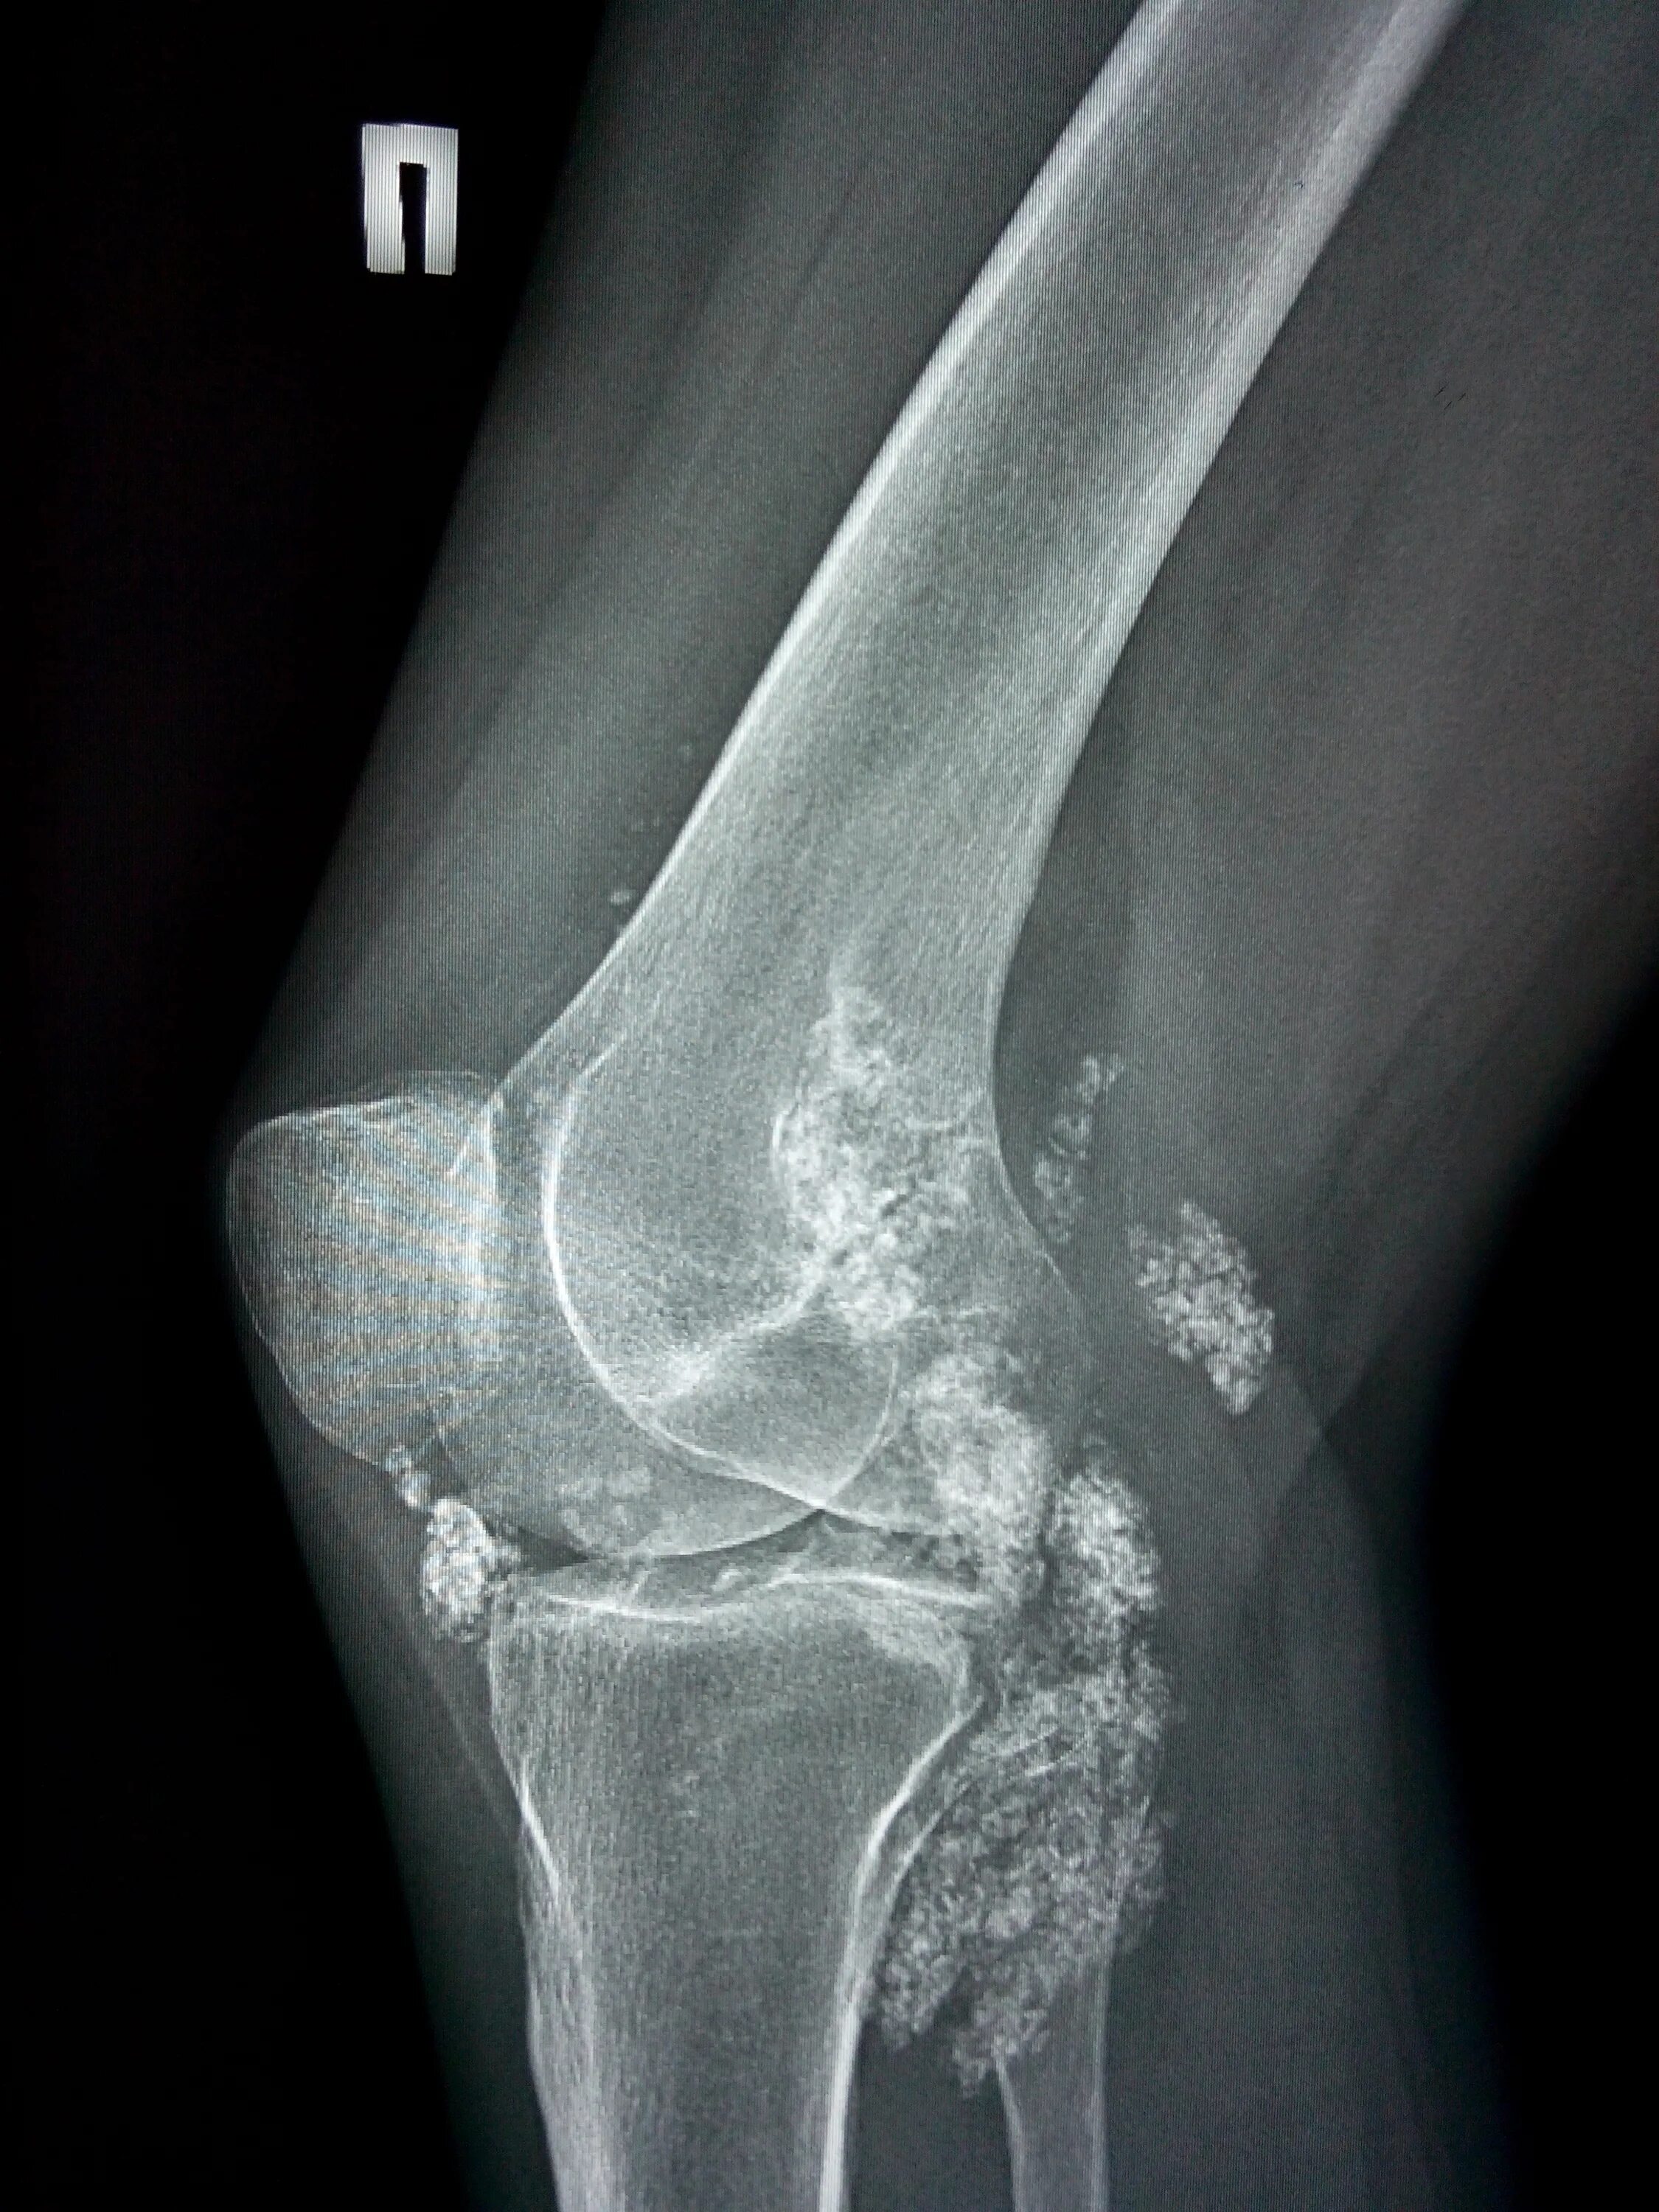

Оссифицированный миозит